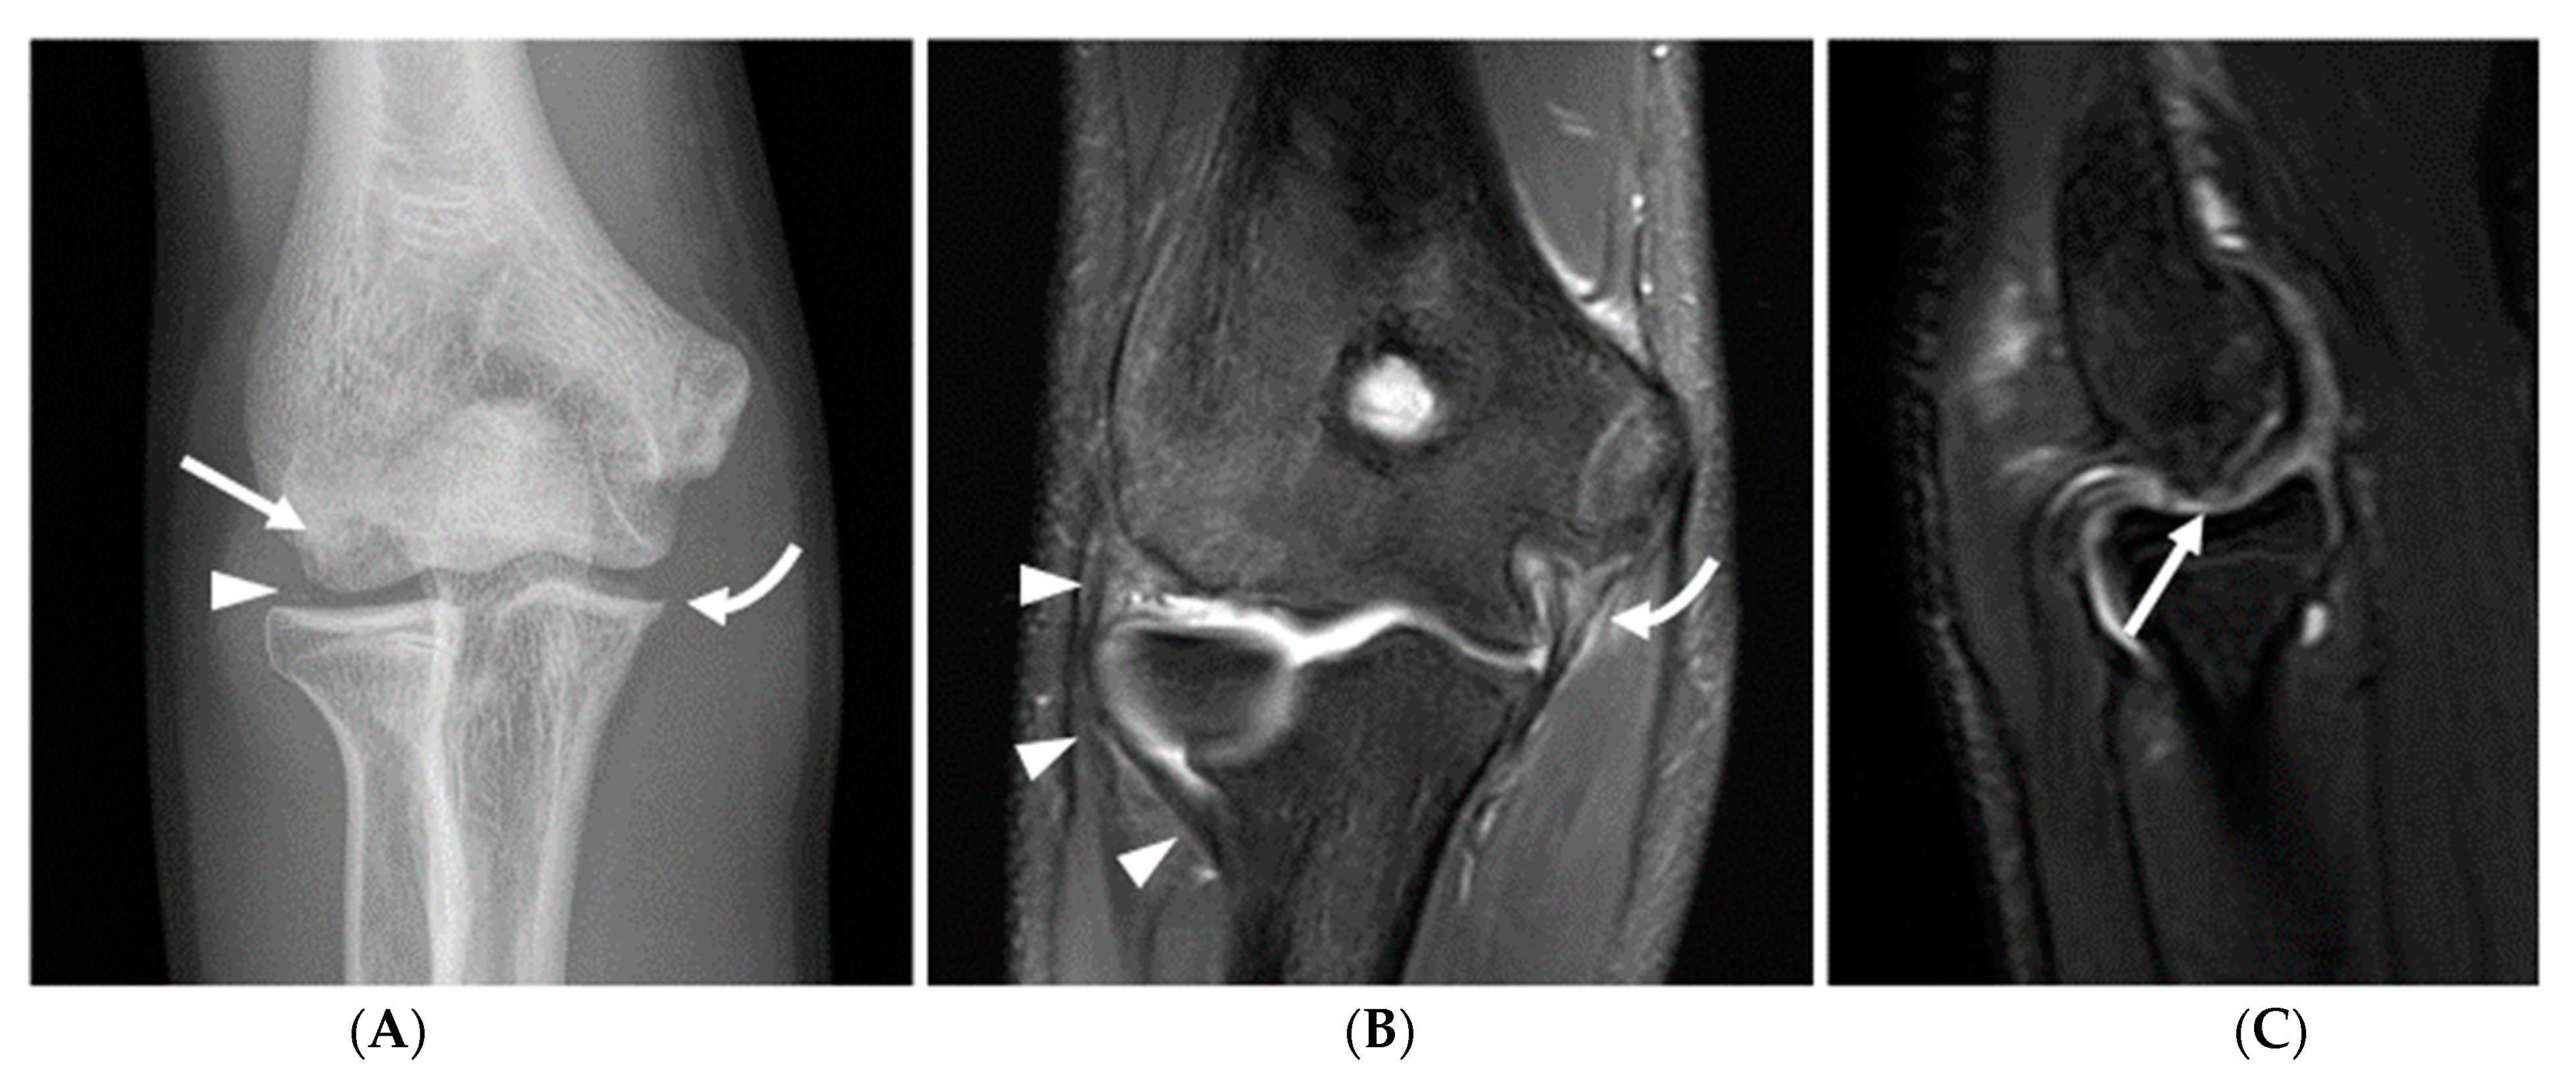

Olecranon apophysitis was also only seen in athletes in subgroup 1 (Figure 5), with the exception of one athlete in subgroup 3 who had a chronic injury with associated nonunion of the olecranon apophysis, and olecranon stress reaction or fractures were observed with a higher frequency in subgroups 1 and 2 (12% and 24%, respectively), with a chronic injury seen in a single subject in subgroup 3. Other findings consistent with repetitive loading secondary to posteromedial shear and resultant degenerative changes in the posterior humeroulnar joint were observed with high frequency across all age groups, although this progressively increased with age. Specifically, humeroulnar osteophytes were observed in 62% of subjects in subgroup 1, 72% of subjects in subgroup 2, and 74% of subjects in subgroup 3 (Figure 6). This is in contrast to controls, where only 17% of subjects demonstrated posterior humeroulnar osteophytes.

Figure 5.

A 15-year-old right-hand-dominant male baseball pitcher with right posterior elbow pain. (A) Sagittal fat-saturated T2-weighted image of the right elbow demonstrates irregularity, increased T2 signal and cystic change along the olecranon physis (open arrow), with periphyseal bone marrow edema, compatible with olecranon apophysitis. (B) Radiographic comparison of the bilateral elbows demonstrates physeal widening, irregularity, and delayed closure of the physis (open arrow) compared with the physis of the asymptomatic left elbow (arrow), which is partially fused superiorly.

Figure 6.